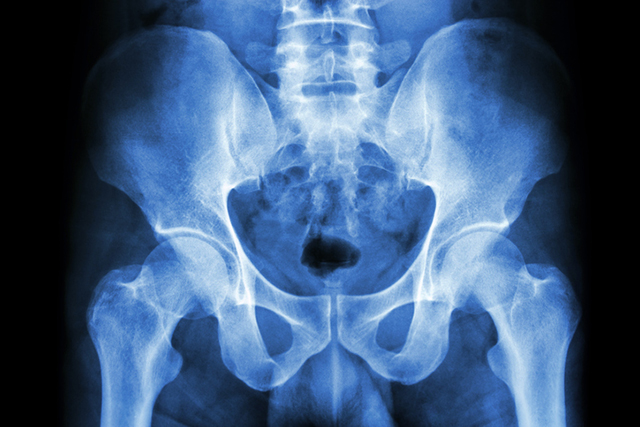

고관절은 골반 끝에서 사타구니 쪽으로 검지 길이만큼 내려간 곳에 있는 관절을 말한다. 골반과 허벅지 대퇴골을 연결해 윗몸 무게를 지탱하고, 달리기처럼 과격한 운동을 견뎌내게 한다.

고관절은 누워있는 순간을 제외하고 24시간 움직이고 활동하기에 다치기도 쉽다. 특히 낙상 사고 시 엉덩이 충격이 가해지면 쉽게 금이 가고 부러진다.

특히 고관절은 나이가 들면 골다공증으로 뼈가 약해져 사소한 충격에도 부러지는 골절이 발생하기 쉽다. 노인 인구가 늘어나는 우리나라에서도 고관절 골절로 병원을 찾는 환자가 매년 늘어나면서 고관절 골절 치료와 예방에 대한 중요성이 대두되고 있다.